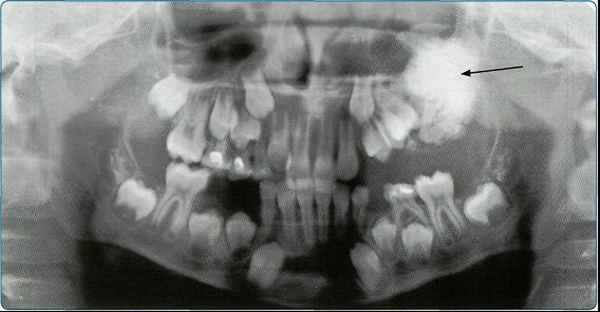

Особенно важно использовать ортопантомографию в детской стоматологии, где она не имеет конкурентов в связи с низкими дозами облучения и большим объемом получаемой информации. В детской практике ортопантомография помогает диагностировать переломы, опухоли, остеомиелит, кариес, периодонтиты, кисты, определять особенности прорезывания зубов и положение зачатков.

На основании панорамных снимков диагностируют кариес и его осложнения, кисты разных типов, новообразования, повреждения челюстных костей и зубов, воспалительные и системные поражения. У детей хорошо определяется состояние и положение зачатков зубов.